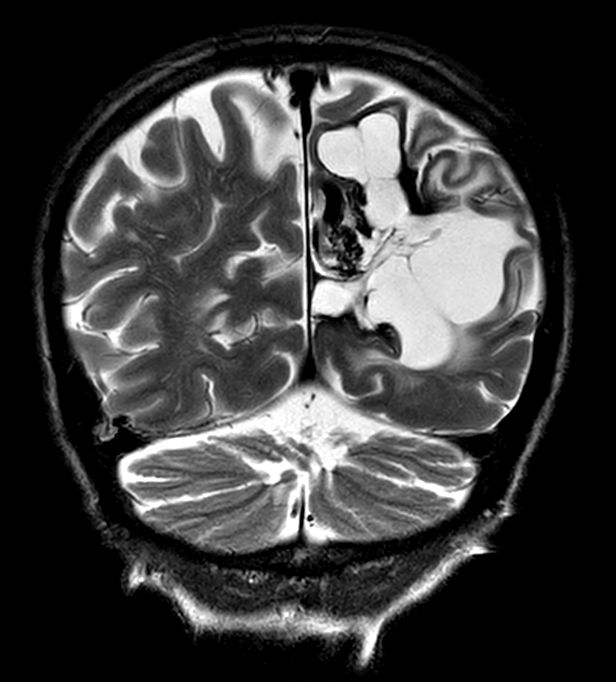

Coronal T2w TSE